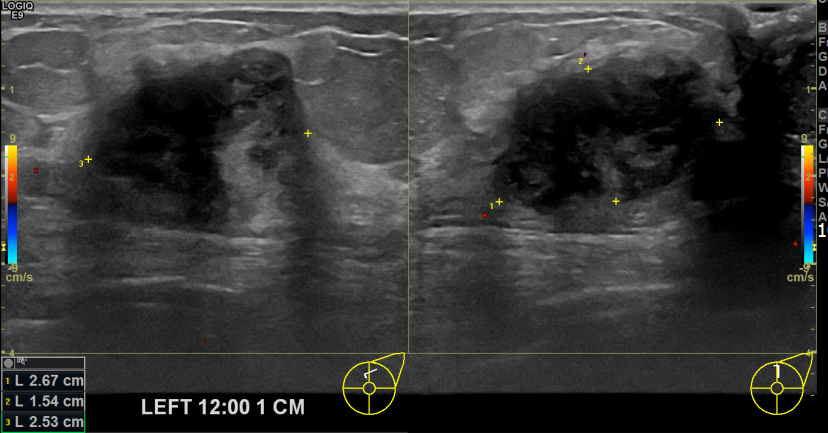

아산유외과개원후 741번째 유방암진단

상기환자 외부검진상 이상소견으로 조직검사권유받고 내원하신 70대 여성분으로 좌측유방멍울 조직검사 시행 후 유방암 진단되었습니다.